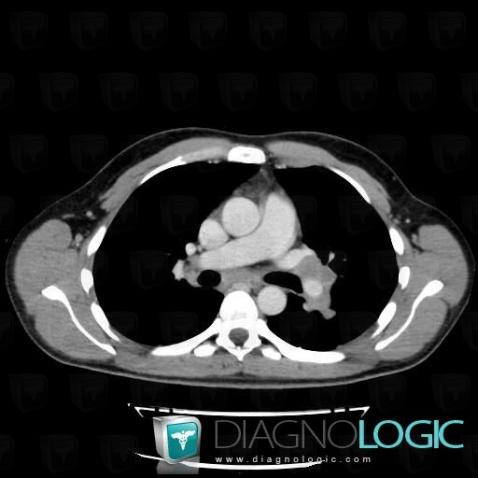

Voici les informations spécifiques à l'image clé ci dessus:

- Diagnostic Lymphome , Localisation(s) Médiastin, comportant les gammes Adénomégalie hilaire